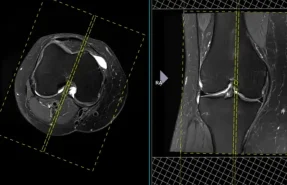

آرتروسکوپی زانو

آرتروز زانوچیست؟ از کجا بفهمیم آرتروز داریم؟ و راه‌های درمان آن را بدانیم.

پارگی منیسک زانو

آسیب رایج در ورزشکاران که معمولا به علت چرخش ناگهانی زانو رخ می‌دهد و باعث درد و تورم در زانو می‌شود.

پارگی رباط صلیبی قدامی

یکی از رایج‌ترین آسیب‌های رباط زانو که می‌تواند باعث ناپایداری و کاهش کارایی زانو شود.